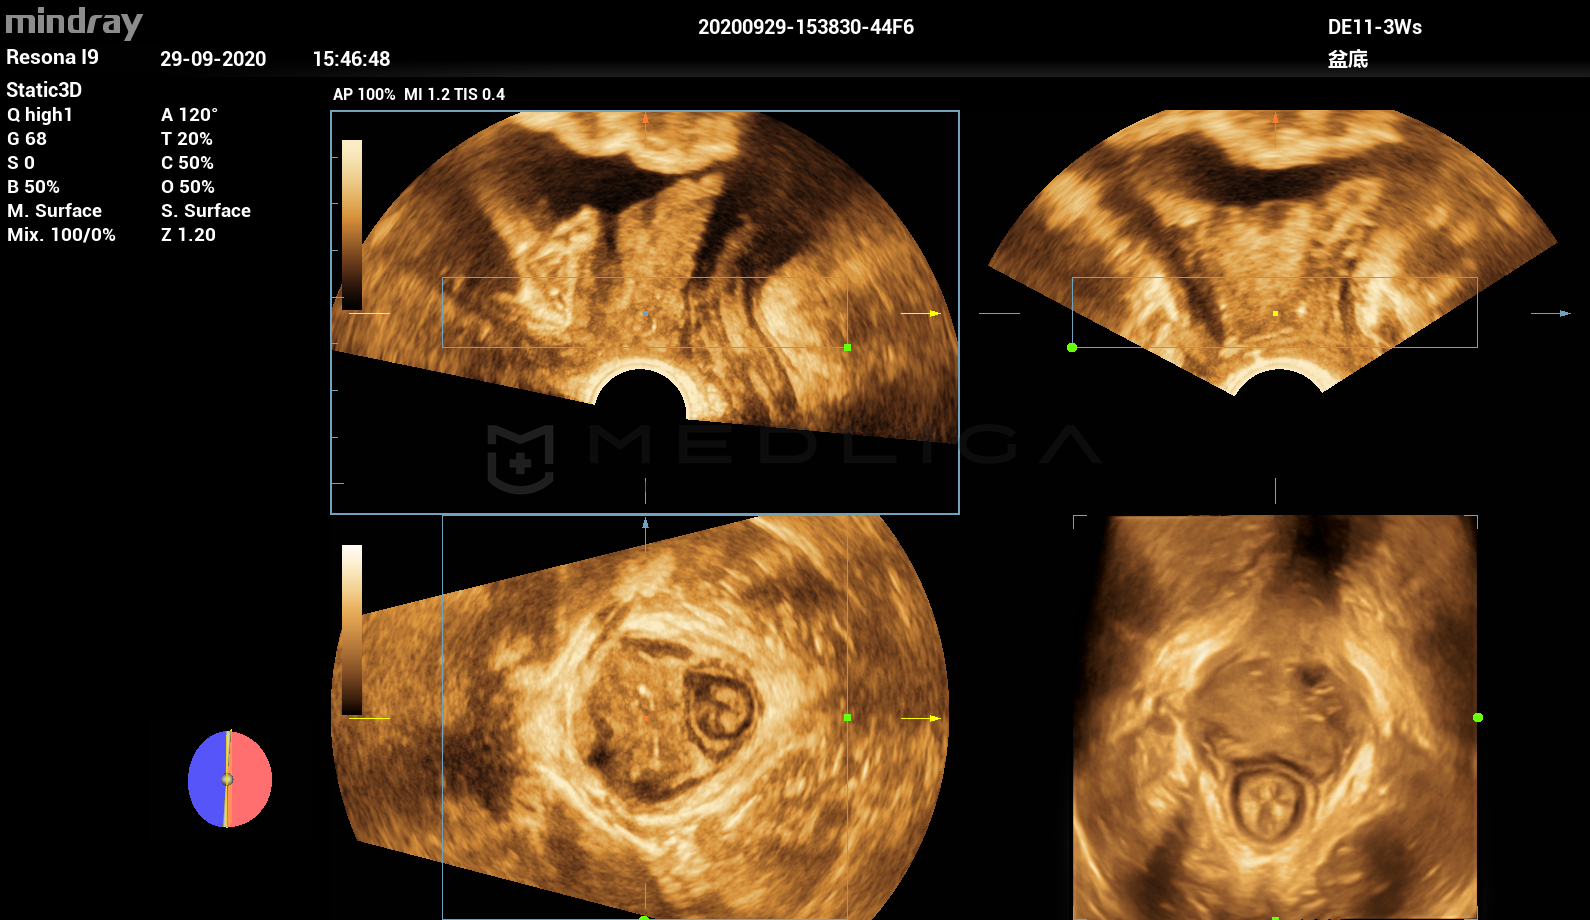

Программное обеспечение для автоматических измерений параметров и оценки функции мышц тазового дна.

Smart Pelvic - новое решение, позволяющее значительно упростить диагностическую процедуру и свести к минимуму время исследования функций мышц тазового дна. Благодаря чрезвычайно простому пользовательскому интерфейсу, программа генерирует стандартную систему координат и автоматически просчитывает все связанные измерения в течение нескольких секунд.